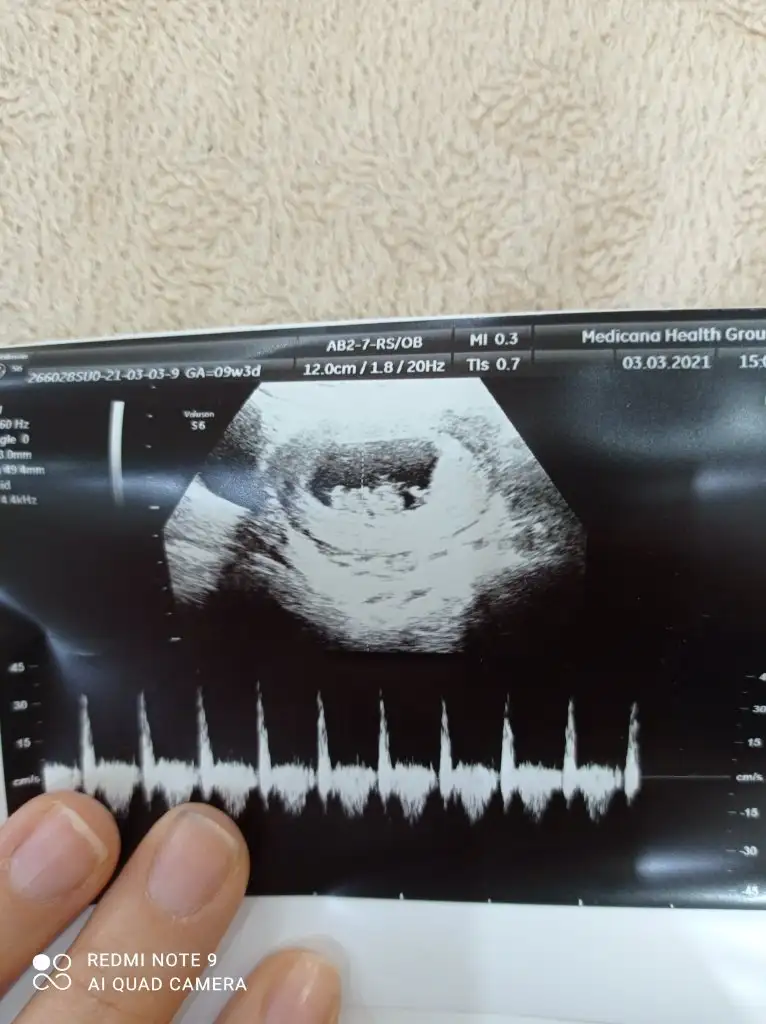

Benimkinede bakarmisiniz 7 haftalikti burda karindan ultrasyonPlesanta solda bebekte solda karindan ultrasyonsa erkek